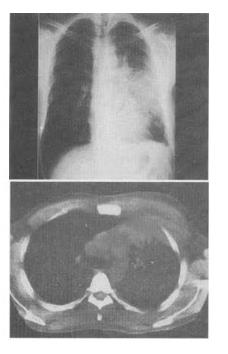

患者男,42岁,胸痛1周余,X线片发现肺部阴影,CT检查如图,最可能的诊断为()。

A:肺部感染

B:肺放线菌感染并脓胸侵犯胸壁

C:肺类风湿病侵犯胸壁

D:肺结核并胸腔积液

E:肺真菌感染并脓胸侵犯胸壁